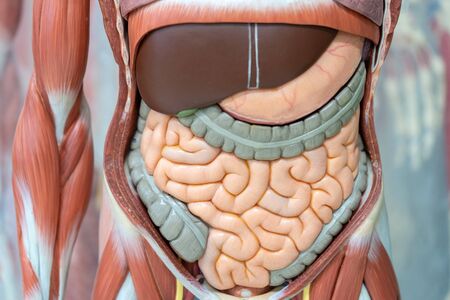

Concept of health care, stomach and intestinal problems